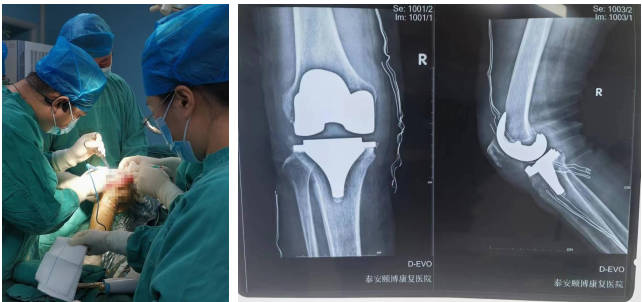

骨科

擅长腰腿疼痛的诊治及四肢骨折、外伤的救治。开展了全膝、髋关节置换术、肘内翻、足外翻畸形矫形术、经皮椎体成形术、复杂手足外伤皮瓣修复术、复杂关节内骨折复位固定术、骨肿瘤切除植骨固定术、椎间孔镜椎间盘髓核摘除术、椎管狭窄椎管减压术。